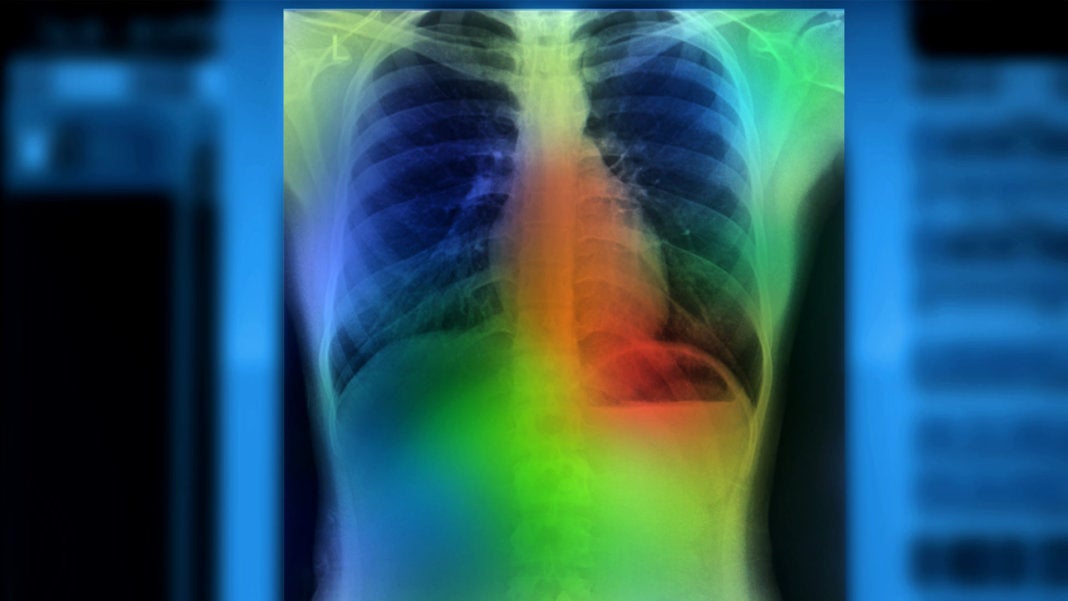

Image Credit: Zapp2Photo / Shutterstock.com